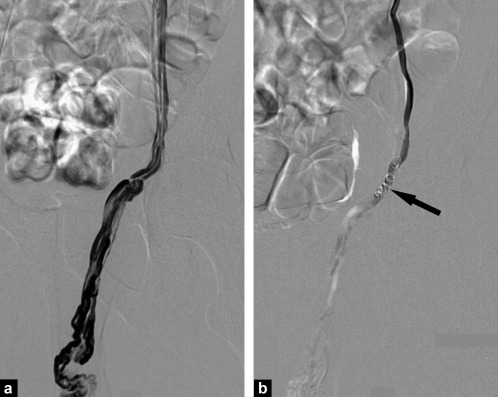

Instead of open surgery, a tiny catheter (<2mm) is inserted into a vein (usually in the arm). Using fluoroscopic guidance, catheter is advanced into abnormal vein. Small coils or plugs are placed to block the faulty veins draining testis. The catheter is then removed and a Band-Aid is applied.

Procedure is done under local anaesthesia. It usually take 45minutes - 1 hr. A thin tube is placed through a vein in the groin or neck. Using X-ray guidance, coils, plugs, or medical glue are placed to block abnormal veins, causing blood flow to be redirected to normal veins.